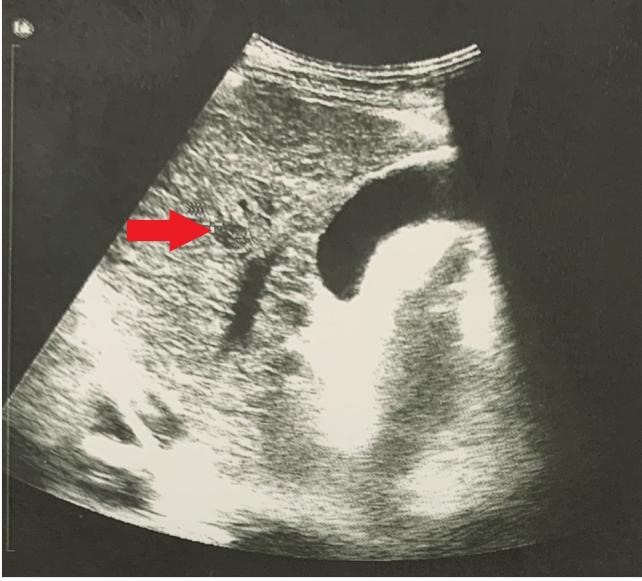

- Cộng hưởng từ gan mật có tiêm thuốc:

Hình ảnh nhu mô gan hạ phân thùy S5 có nốt đường kính 8,5mm tăng nhẹ tín hiệu trên T2W, hạn chế khuếch tán trên DWI, ngấm thuốc mạnh thì động mạnh, có phần thải thuốc thì tĩnh mạch và thì muộn. Tĩnh mạch cửa không giãn, không thấy huyết khối.

Hình 2: Hình ảnh MRI ổ bụng:  nốt hạ phân thùy S5 (vòng tròn màu đỏ) (A: thì động mạch, B: thì tĩnh mạch, C: thì muộn)